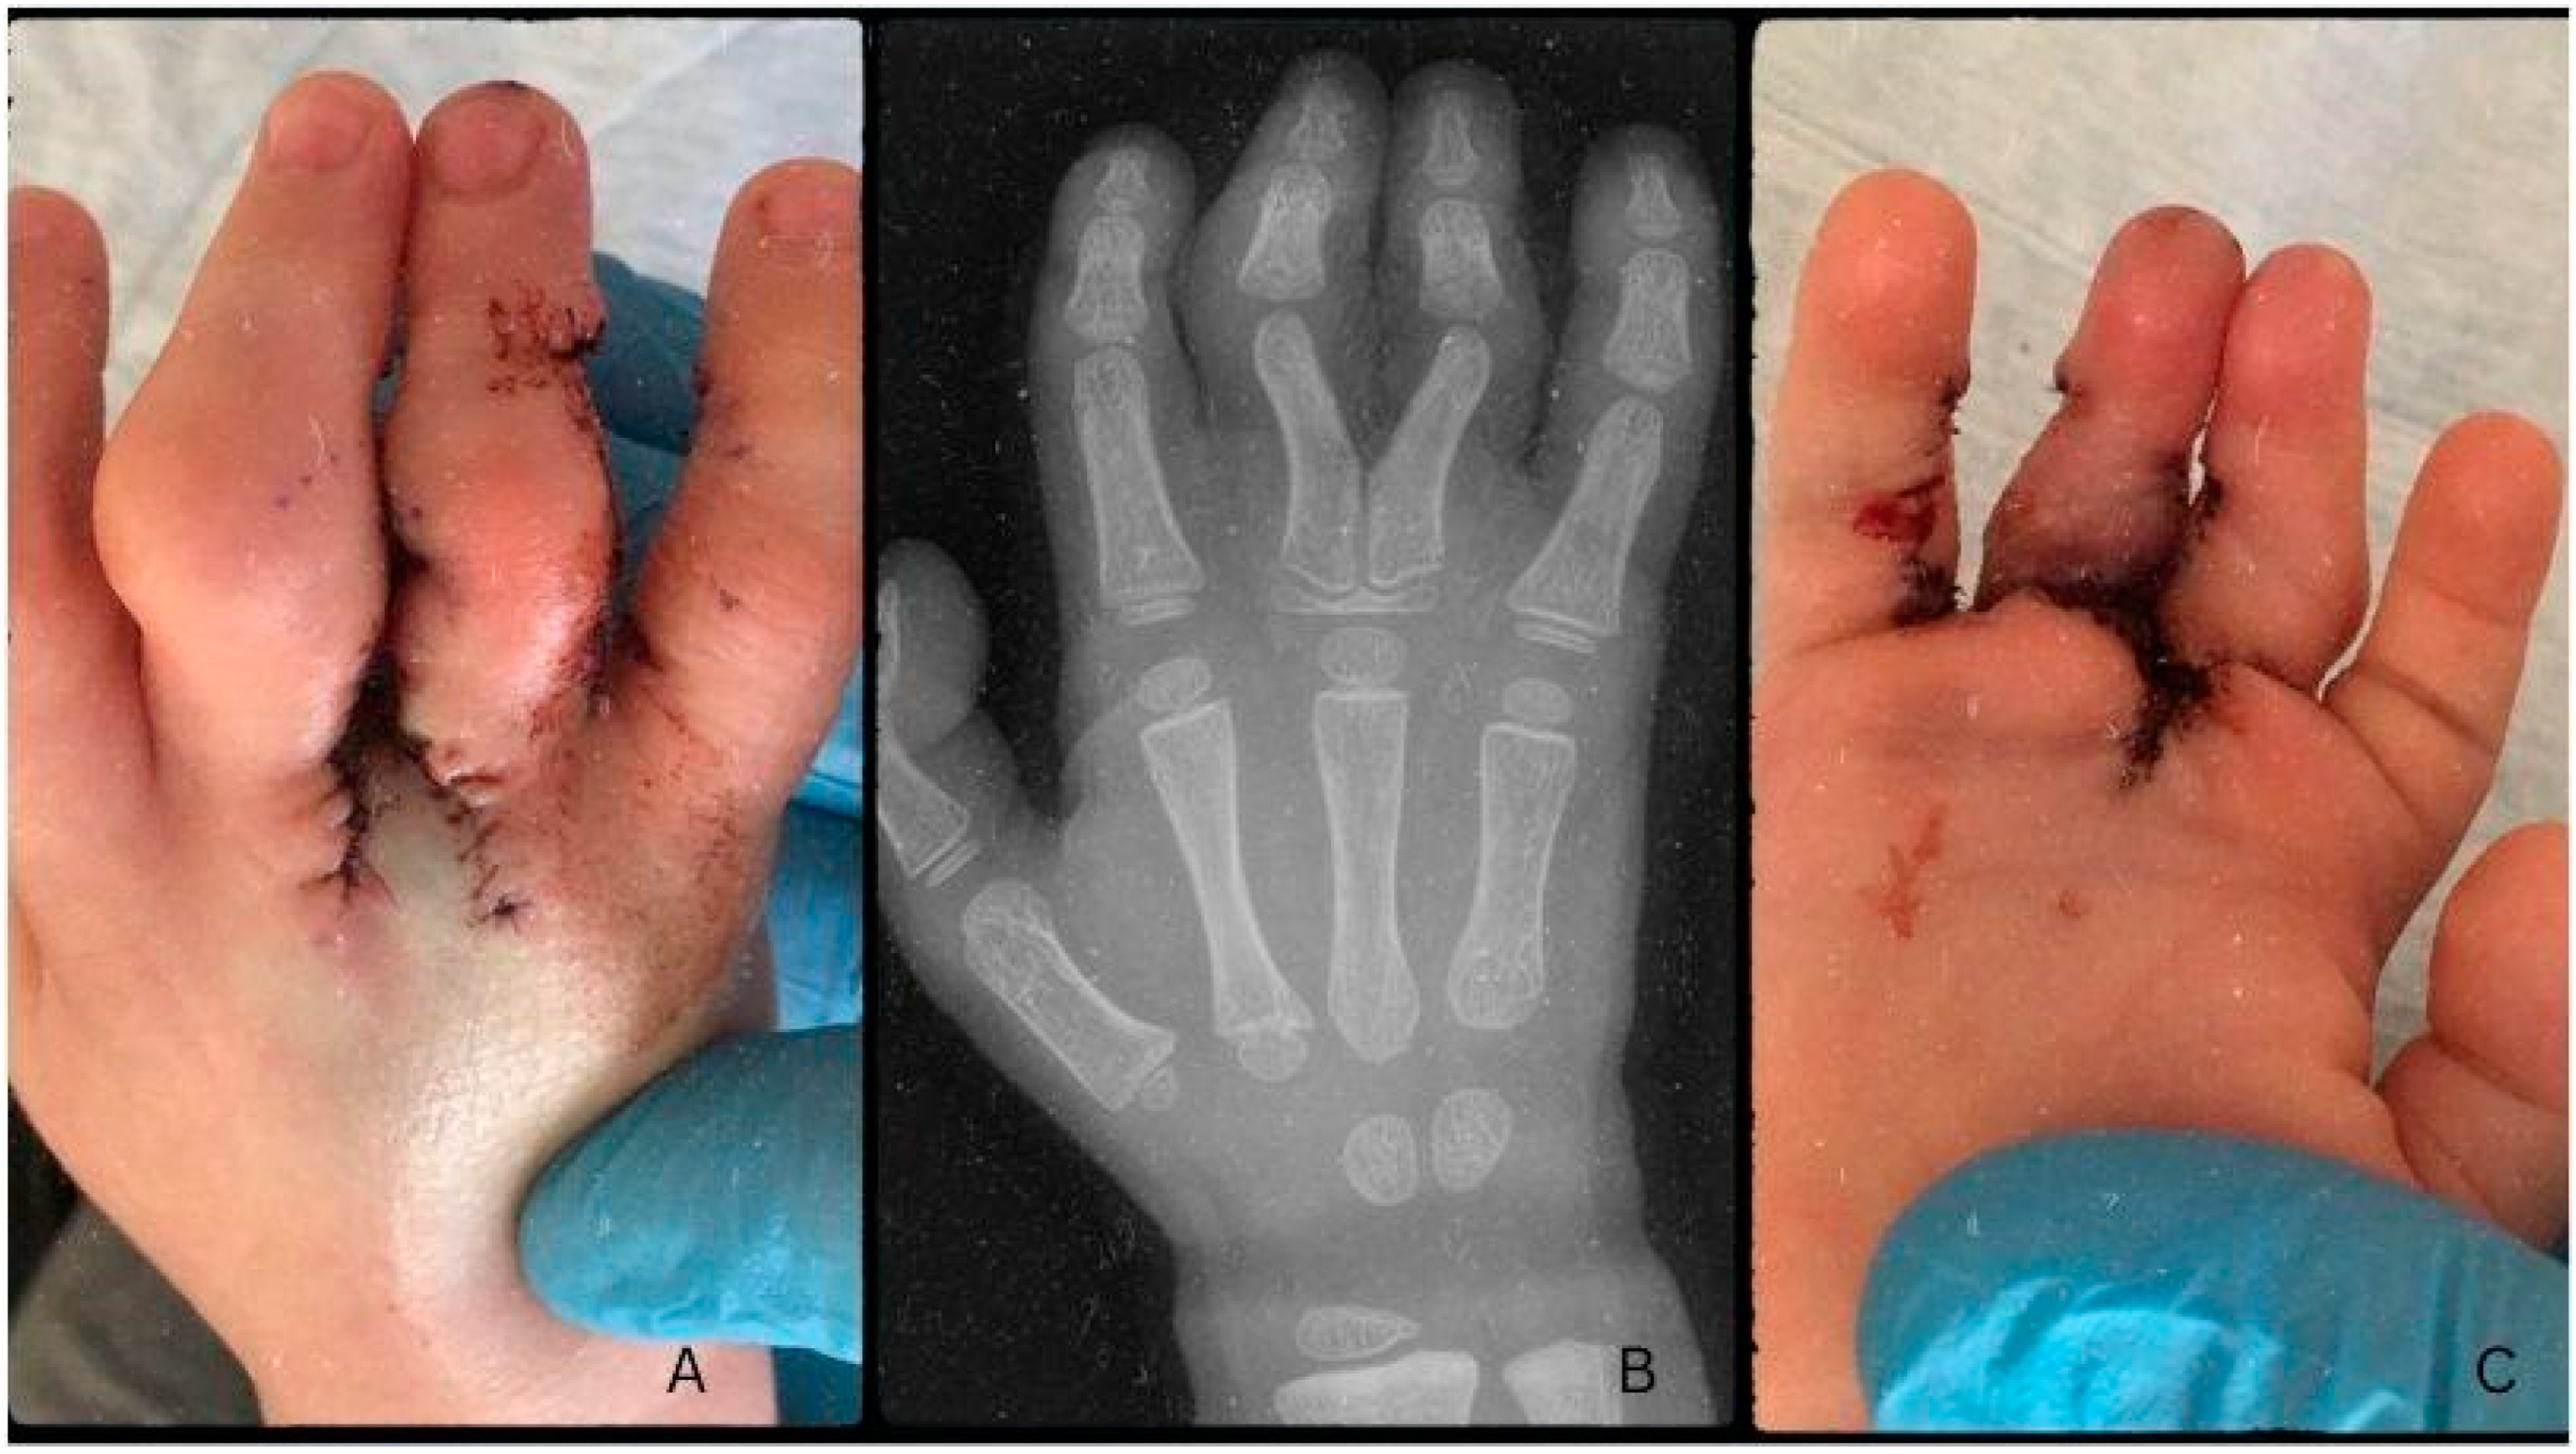

Post-op antibiotic prophylaxis was given in the form of Augmentin (Amoxicillin + Clavulanic Acid) syrup 3x4 ml for seven days. During the early postoperative period, there were no signs of circulatory anomalies and the microcirculation was continuous. The control radiograph described the post-osteotomy state as the fusion of the proximal phalanges’ proximal epiphyses, forming a Y-shape from a common metacarpal (Figure C). One day after surgery, during rebandaging, proper capillary reflex and microcirculation were noted, with non-reactive scarring (Figure 4). On the 3rd day after surgery, the patient was emitted to their home for recovery. On control examination, ten days after surgery, circulation was adequate with proper capillary reflex. On the dorsal surface of the hand, a slight hematoma was visible, with mild swelling and non-reactive scars. Rebandaging and Bacitracin-containing swathing were applied. Three days later, the bandaging was removed and the wound was left to heal on its own two weeks after surgery. Further control examinations on days 21 and 35, corresponding to weeks three and five, noted the proper depth of the IV. interdigital space and adequate circulation of the fingers. The scars remained non-reactive and continued to heal while the swelling went down (Figure 5). The fingers were straight; however, functionality could not be tested yet.

Figure 4. Post-operative images one day after surgery, dorsal side (A) and palmar side (C). Radiograph describes the postoperative state … weeks after the surgery (B).